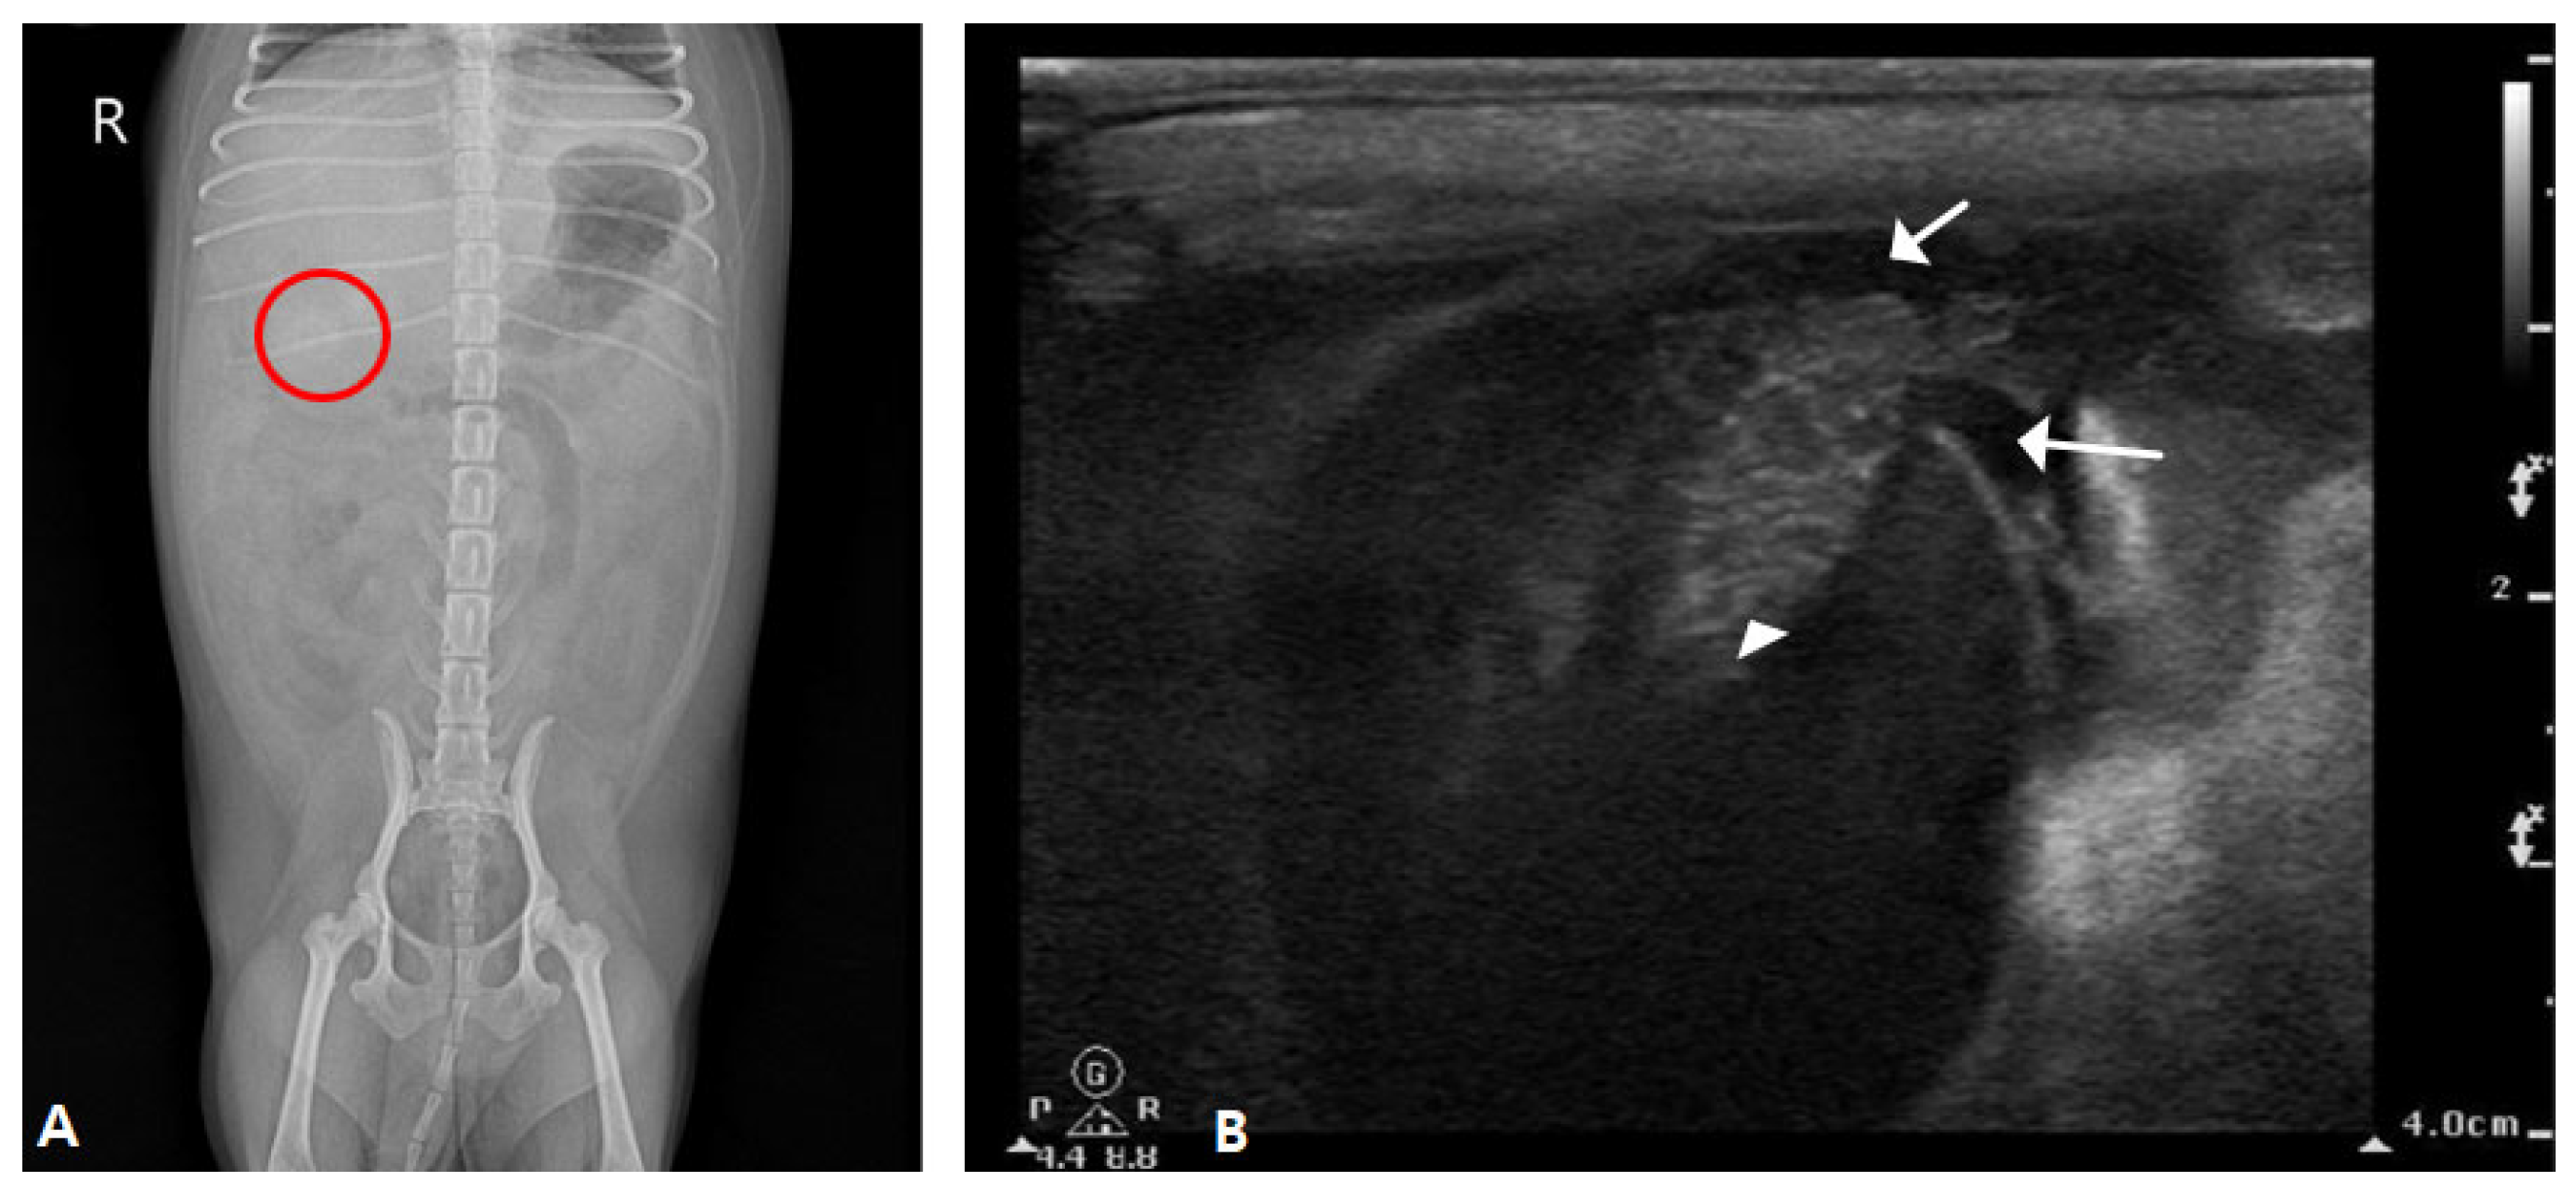

2.1. Case I